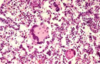

Highly contagious and often fatal respiratory disease of pigs 2-5 months of age characterized by fibrinous bronchopneumonia on the dorsal area of the caudal lung lobe.

Porcine Contagious Pleuropneumonia

Etiology of Porcine Contagious Pleuropneumonia

Actinobacillus pleuropneumoniae